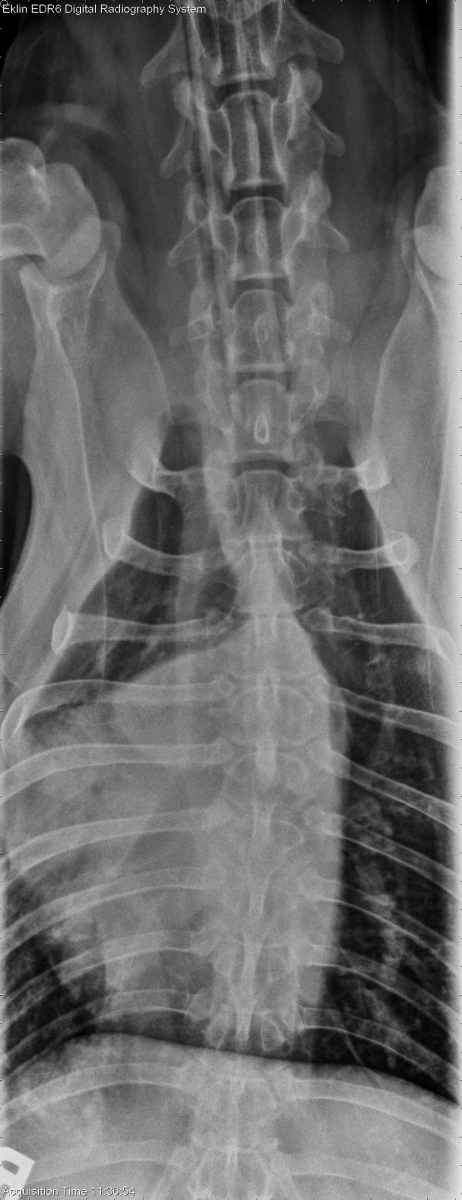

VD Spine

There are multiple sites of spondylosis deformans including T9-10, T13-L1, and the lumbosacral junction. There is sclerosis and irregularity of multiple caudal thoracic and lumbar vertebral articular facets. There is sclerosis and an irregular cranial and caudal contour of the dorsal spinous process of T4. There is beginning lysis of the T2, T3 & T5 dorsal spinous processes.

Lysis of spinous processes from T2 -T5; soft tissue neoplasia with secondary bone lysis is a primary consideration.

Soft tissue sarcoma invading the dorsal spinous processes bilaterally and spinal canal on the left side at T4.